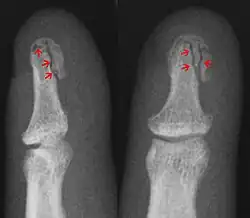

- Avulsion fracture – a fracture where a fragment of bone is separated from the main mass

| Avulsion fracture | A fragment of bone is separated from the main mass (image shows a Busch fracture) | |||